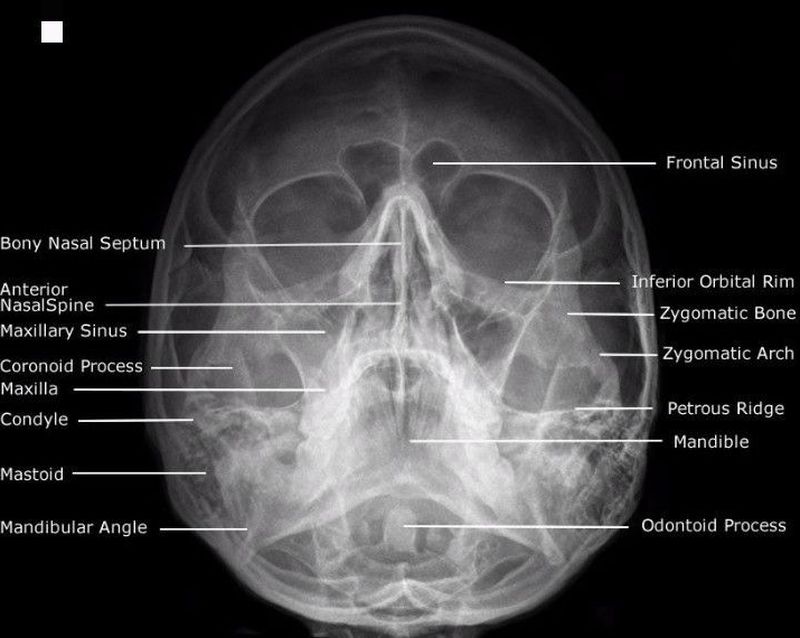

Waters view

Occipitomental view showing air sinuses.